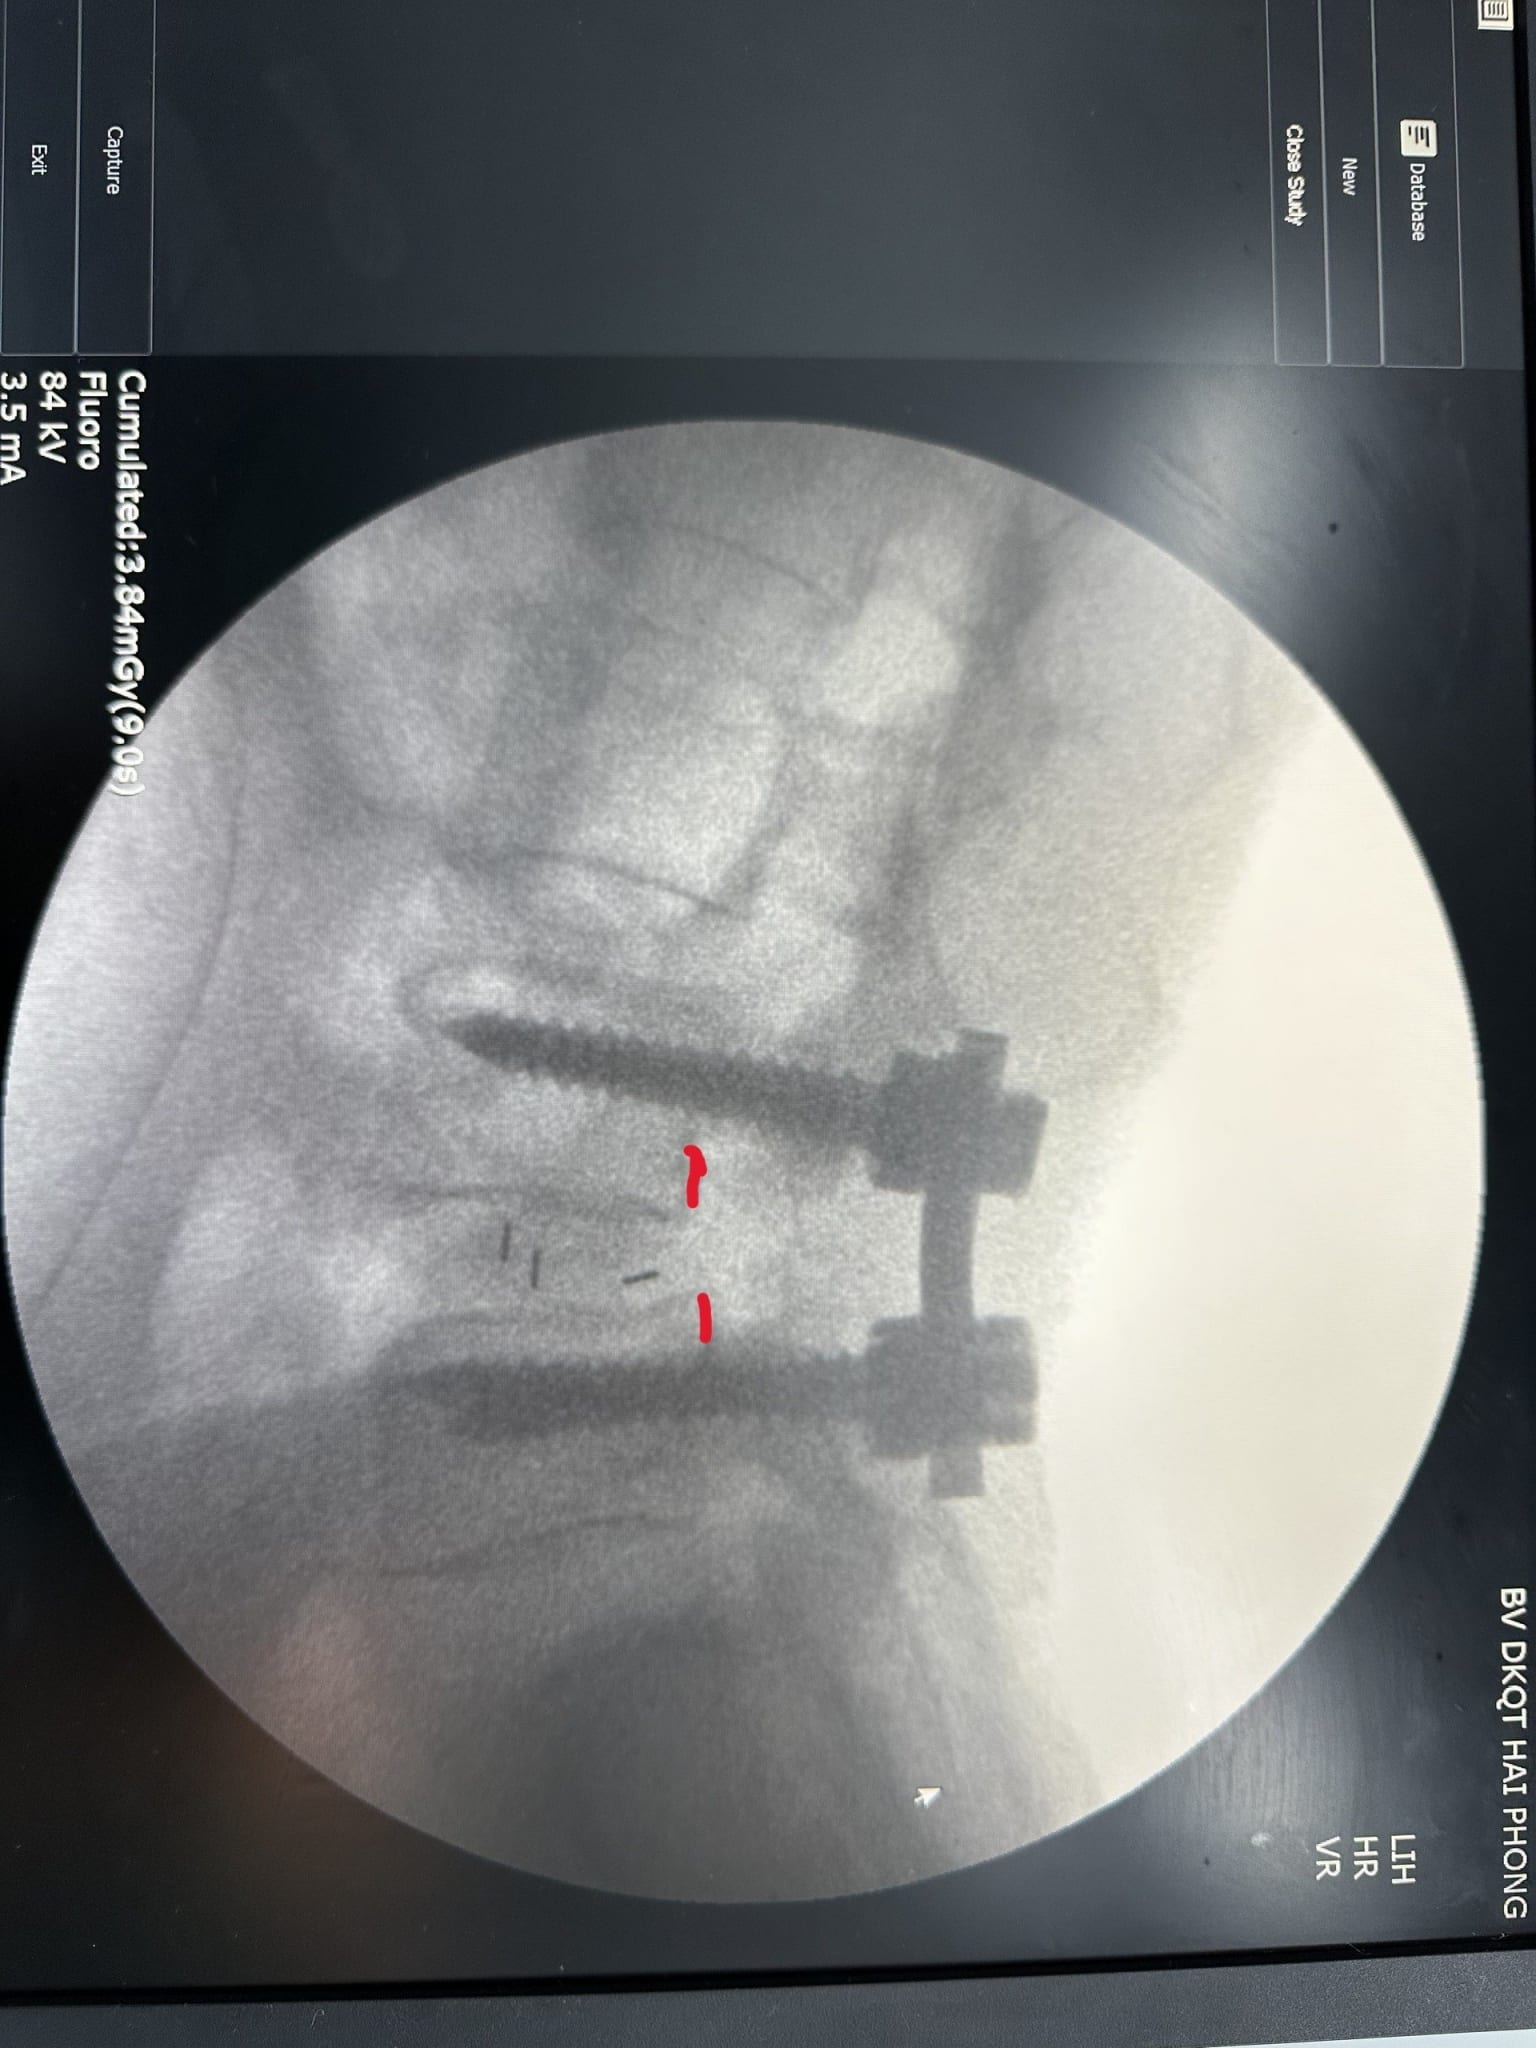

Nhanh chóng, bệnh nhân được điều trị bằng phương pháp: Phẫu thuật cố định cột sống L45, giải ép thần kinh, nắn trượt đốt sống, hàn xương liên thân đốt L45. Ca phẫu thuật diễn ra thuận lợi theo đúng kế hoạch. Sau phẫu thuật, bệnh nhân hết đau và tê chân, có thể đeo đai hỗ trợ và tập phục hồi chức năng ngay ngày thứ 2 sau mổ.

- Hình ảnh sau mổ